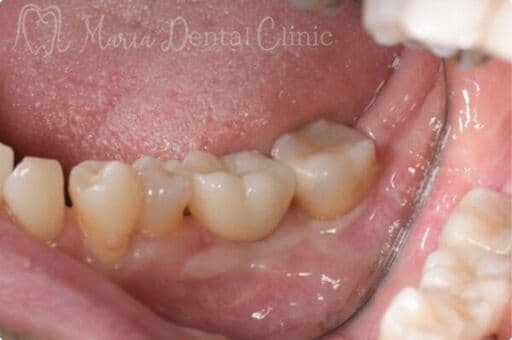

サイナスリフトの症例

【症例】サイナスリフトで骨を増やし、奥歯の支えを回復したインプラント治療

本症例の患者様は、右側の歯を抜歯した後そのまま放置していたことで噛み合わせが大きく乱れ、右上の歯周病が進行して抜歯に至りました。抜歯後は上顎洞に近接して骨量が著しく不足していたため、サイナスリフトによって新たな骨を増やし、インプラントを支える土台を再建しました。十分な骨量を確保することで、奥歯の咬合支持を回復した症例です。

before

after

治療内容 サイナスリフト、インプラント、矯正治療

治療期間 10ヶ月

治療回数 4回(他、抜糸、術後3ヶ月後、1年後の経過観察等を除く)

治療費用 3,300,000円(税込、サイナスリフト他、矯正治療を含む)

症例から言えること

本症例は、抜歯後の欠損部を放置すると歯が傾斜し、咬合支持が失われることで噛み合わせ全体が乱れ、別の部位の歯周病が急速に悪化することを示しています。さらに、こうした連鎖は将来的な大きな咬合崩壊につながる可能性があります。一方、骨量不足があってもサイナスリフトによりインプラントを支える骨を再建することで、機能を回復し、咬合の安定を取り戻すことが可能です。複雑な症例ほど、早期の診査・診断と適切な処置が咬合崩壊を防ぐ鍵となります。